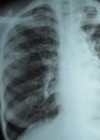

24.martā tiek atzīmēta Pasaules tuberkulozes diena. Kā norāda LTPSĀA valdes priekšsēdētājs, asoc. prof. Alvils Krams, saslimstība ar tuberkulozi valstī pēdējos gados ir pieaugusi – 2011. gadā ar saslima 788, savukārt 2012. gadā jau par 12% vairāk – 880.

Saslimstība pieaug arī bērnu un pusaudžu vidū (lūdzu skatīt attēlus - datu avots: VM „Slimību Profilakses un kontroles centrs” un SIA RAKUS stacionārs „Tuberkulozes un plaušu slimību centrs”).

Pasaules Veselības organizācija pēc īpašas formulas veic aprēķinus, cik % no tuberkulozes gadījumiem valstī tiek diagnosticēti. Ja līdz 2010. gadam Latvijā tika diagnosticēti 90-100%, tad 2011. gadā – tikai 75% pirmreizēji ar tuberkulozi saslimušo. Pēc PVO aprēķiniem 2011. gadā valstī netika diagnosticēti 300-400 tuberkulozes gadījumi, no kuriem 150-200 slimniekiem ir atklāta (bacilāra) tuberkulozes forma. Nav nekāda pamata uzskatīt, ka 2012. gadā šie rādītāji ir bijuši labāki.

Visefektīvākā intervence tuberkulozes izplatības ierobežošanā ir saslimšanas gadījumu (īpaši, bacilāro) savlaicīga diagnostika un izārstēšana. Nacionālais Veselības dienests reģionos līgumu slēdz ar veselības iestādēm, kuru akcionāri gandrīz visos gadījumos ir pašvaldības. No veselības iestāžu vadības (tātad arī no Jums) ir atkarīgs, vai no kopējās rentgenoloģisko izmeklējumu kvotas pietiekams skaits tiek izdalīts savlaicīgai tuberkulozes diagnostikai. Vai pietiks resursu telefona zvaniem un vēstulēm iespējamo tuberkulozes slimnieku meklēšanai. Vai šajā darbā palīdzēs ģimenes ārsti un sociālie darbinieki (tuberkuloze visbiežāk skar tieši dzīves pabērnus).